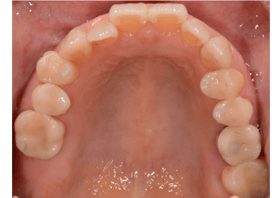

After

ホワイトニングの後、オールセラミッククラウン、セレックを用いた男性の場合

| 治療内容 | ホワイトニング治療後にオールセラミッククラウンとセレックによる審美治療を行いました。 |

| 治療期間・回数 | 1.5ヶ月・7回 |

| 治療費用 | 390,000円(税込) |

| リスク・副作用 | ・被せた歯でない場合、ホワイトニングの効果が約1年経過後から若干暗くなってくることもあり、その場合、再処置(有料)で受診される方がおられます。 ・保険適用ができない自費診療です。 |